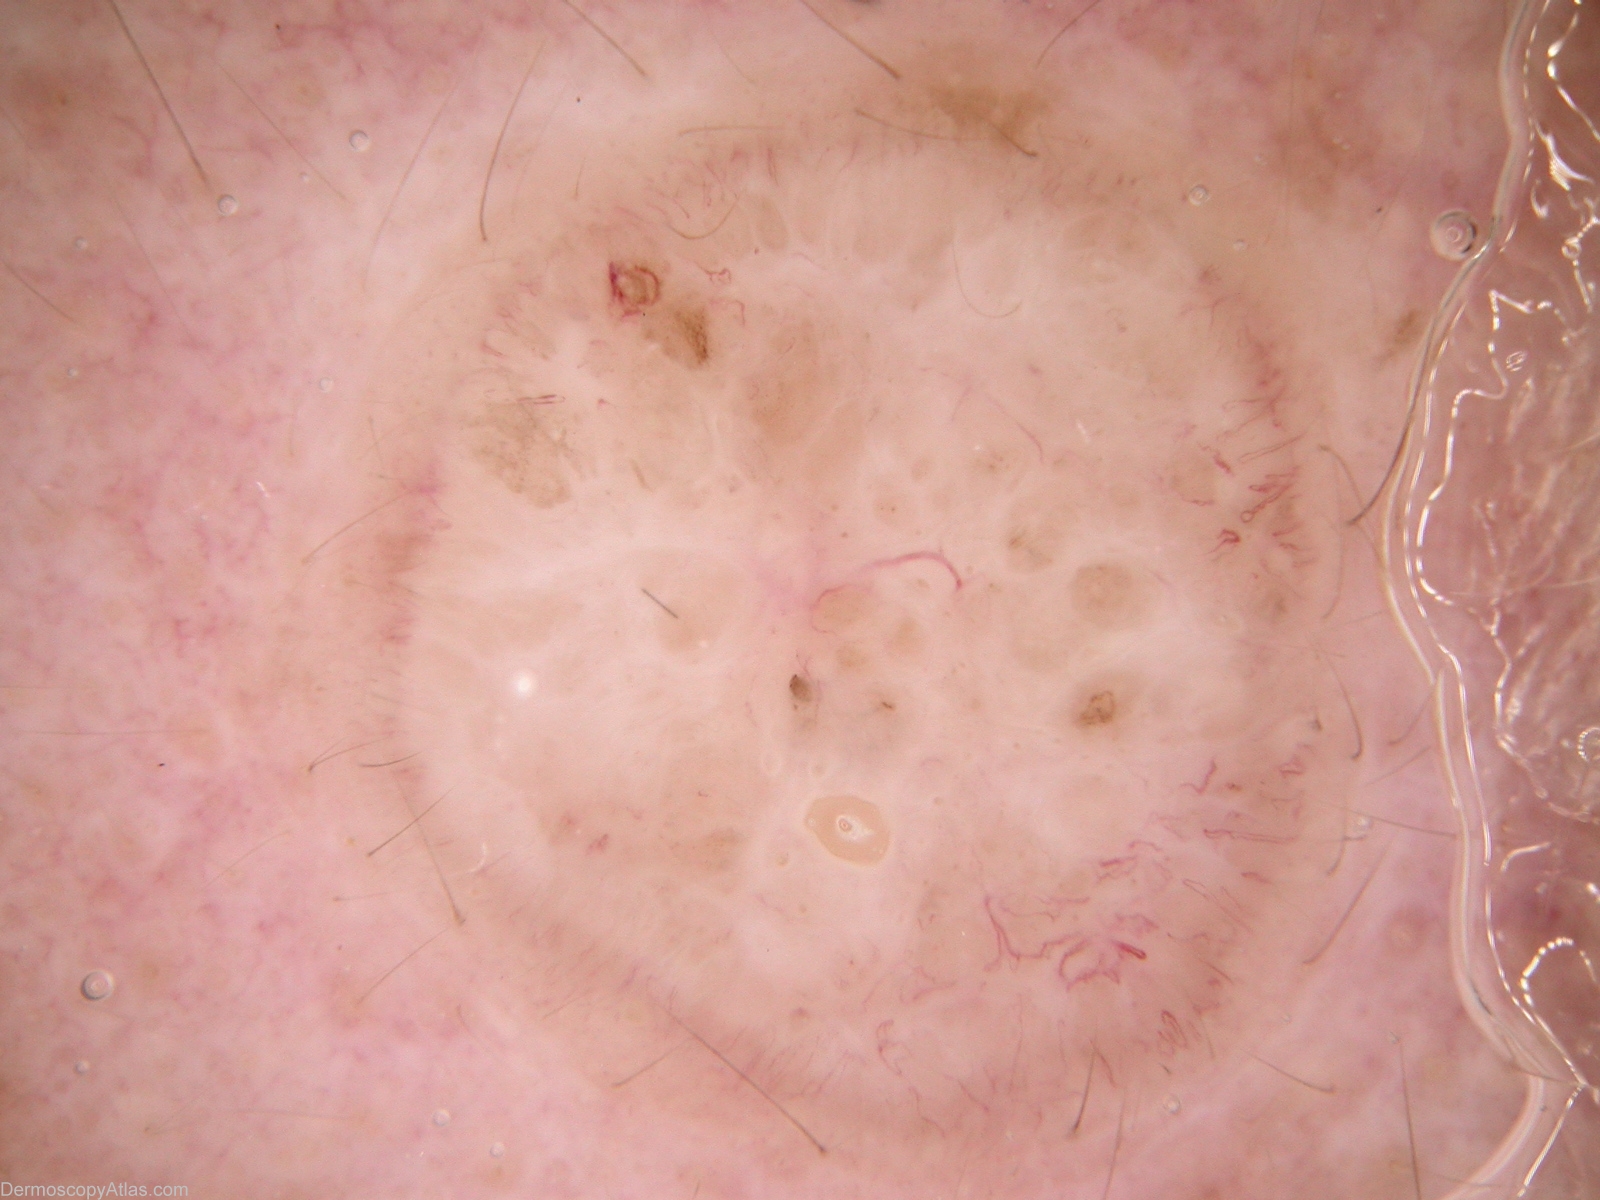

Diagnosis - BCC - Solid

Diagnosis: BCC - Solid